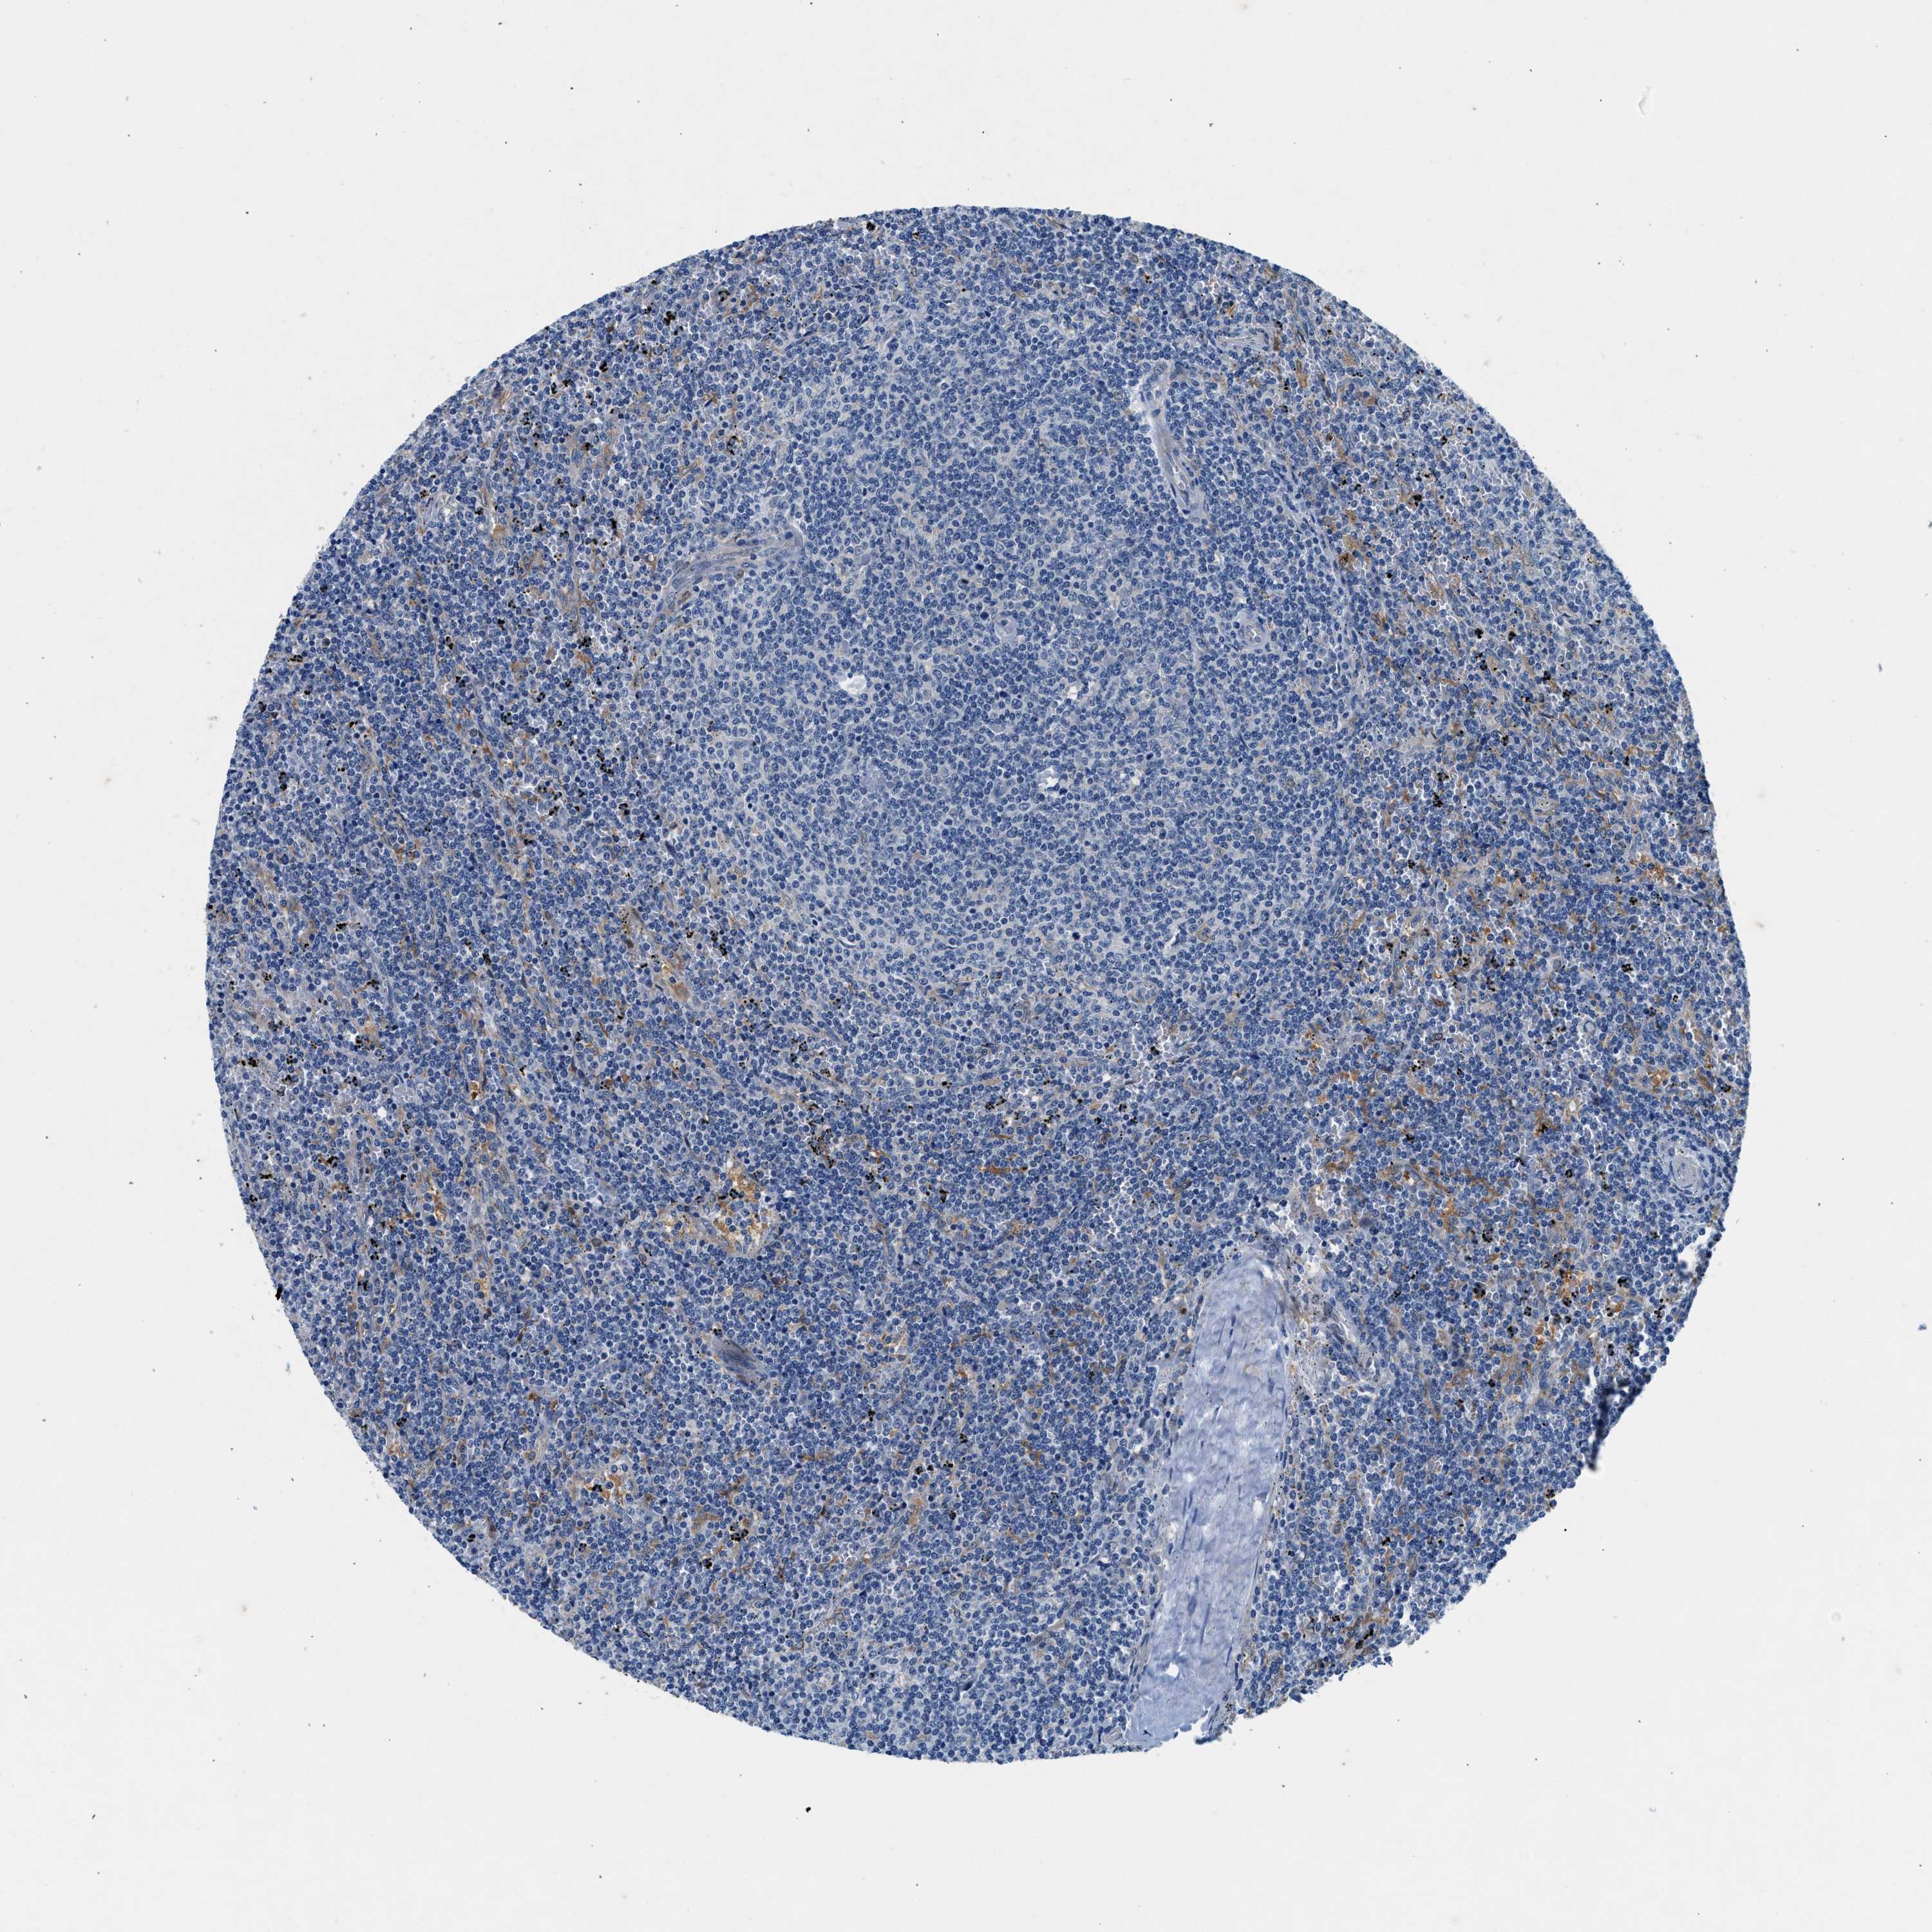

CANCER LYMPHOMA Show tissue menu

LYMPHOMA - Protein expressioni

A mouse-over function shows sample information and annotation data. Click on an image to view it in a full screen mode. Samples can be filtered based on level of antibody staining by selecting one or several of the following categories: high, medium, low and not detected. The assay and annotation is described here.

Antibody stainingi

Antibody staining in the annotated cell types in the current human tissue is reported as not detected, low, medium, or high, based on conventional immunohistochemistry profiling in selected tissues. This score is based on the combination of the staining intensity and fraction of stained cells.

Each image is clickable and will lead to virtual microscopy that enables deeper exploration of all samples and also displays staining intensity scores, fraction scores and subcellular localization as well as patient and tissue information for each sample.

Antibody HPA016867

Antibody HPA018271

Hodgkin's disease, NOS

Malignant lymphoma, non-Hodgkin's type, High grade

Malignant lymphoma, non-Hodgkin's type, Low grade